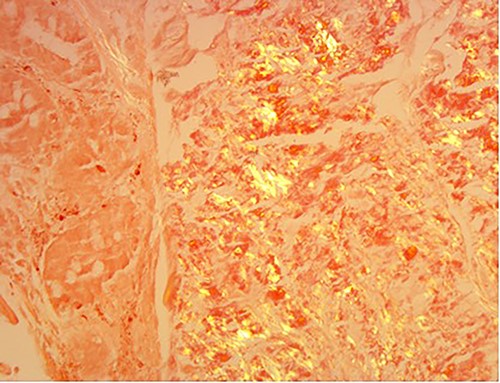

A 76-year-old lady presented to the outpatient clinic with a history of lower abdominal bloating and lethargy for 1 week. The patient denied abdominal pain, nausea, altered bowel habits or GI bleeding. Her past medical history included gastroesophageal reflux disease, ulcerative colitis and a previous hysterectomy. Physical examination exhibited pallor of the conjunctiva, distended abdomen with visible peristalsis on inspection but soft, non-tender on palpation and absence of ascites. Laboratory testing found normocytic normochromic anaemia, thrombocytosis and a positive myeloma screen with elevated kappa to lambda free light chain ratio despite normal renal and liver function. An ultrasound of the abdomen was unremarkable. Computed tomography (CT) with IV contrast of the abdomen revealed diffuse thickening of the small and large bowel with the small bowel dilated throughout. Magnetic resonance imaging of the small bowel showed multiple abnormally thickened loops of the jejunum and proximal ileum with a maximal wall thickness of 0.9 cm (Figs 1 and 2). Gastroscopy revealed severe distal oesophagitis, the stomach contained patchy telangiectasia and gastritis with sloughy mucosa at the incisura in addition to duodenitis with stricture at the second part of duodenum (D2) (Figs 3 and 4). Histopathology from the biopsies of the gastric incisura, D2 and the proximal jejunum displayed reactive changes with intramucosal haemorrhage and extensive deposition of pink amorphous, eosinophilic material on haematoxylin & eosin (H&E) stain. The deposits were predominantly seen in the proximal jejunum with a positive Congo red stain showing apple-green birefringence under polarized light (Figs 5 and 6). The patient was referred to Haematology, and a bone marrow aspirate and trephine biopsy revealed proliferation of 15% mature plasma cells consistent with the diagnosis of myeloma.

High power of proximal jejunum biopsy showing extensive submucosal deposition of pink amorphous material (H&E ×20).

Amyloid stain on proximal jejunum biopsy as seen under polarized light showing apple-green birefringence (Congo Red ×20).